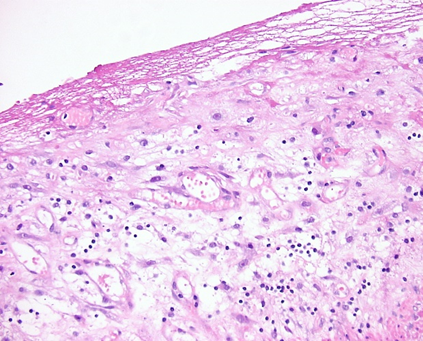

Abb.2: Histologisches Präparat der Appendixschleimhaut ohne Entzündungszeichen.